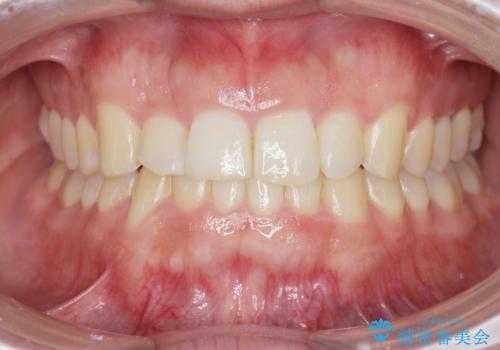

前歯のスペース不足により1本だけ後方に位置している状態でしたが、しっかりとスペースを確保し配列することができました。

- 2年6ヶ月

- 治療回数

- 10-30回